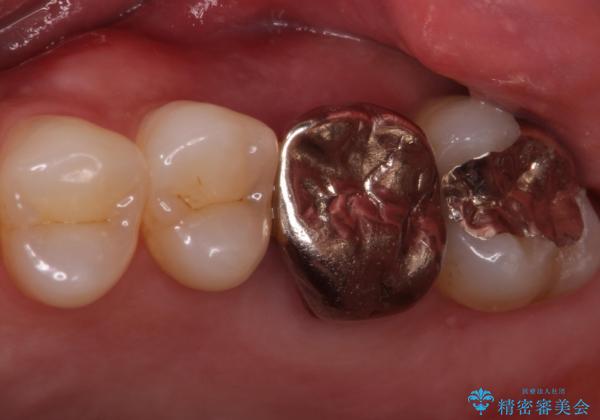

- 左上567:仮歯11,000円×3本、ジルコニアクラウン(スタンダード):121,000円×3本 合計396,000円費用は治療当時の料金となります

ブリッジでの修復は、抜歯後に歯がなくて噛みにくい期間が一切ありません。

歯茎の状態も良く、適合の良いブリッジを装着することができました。